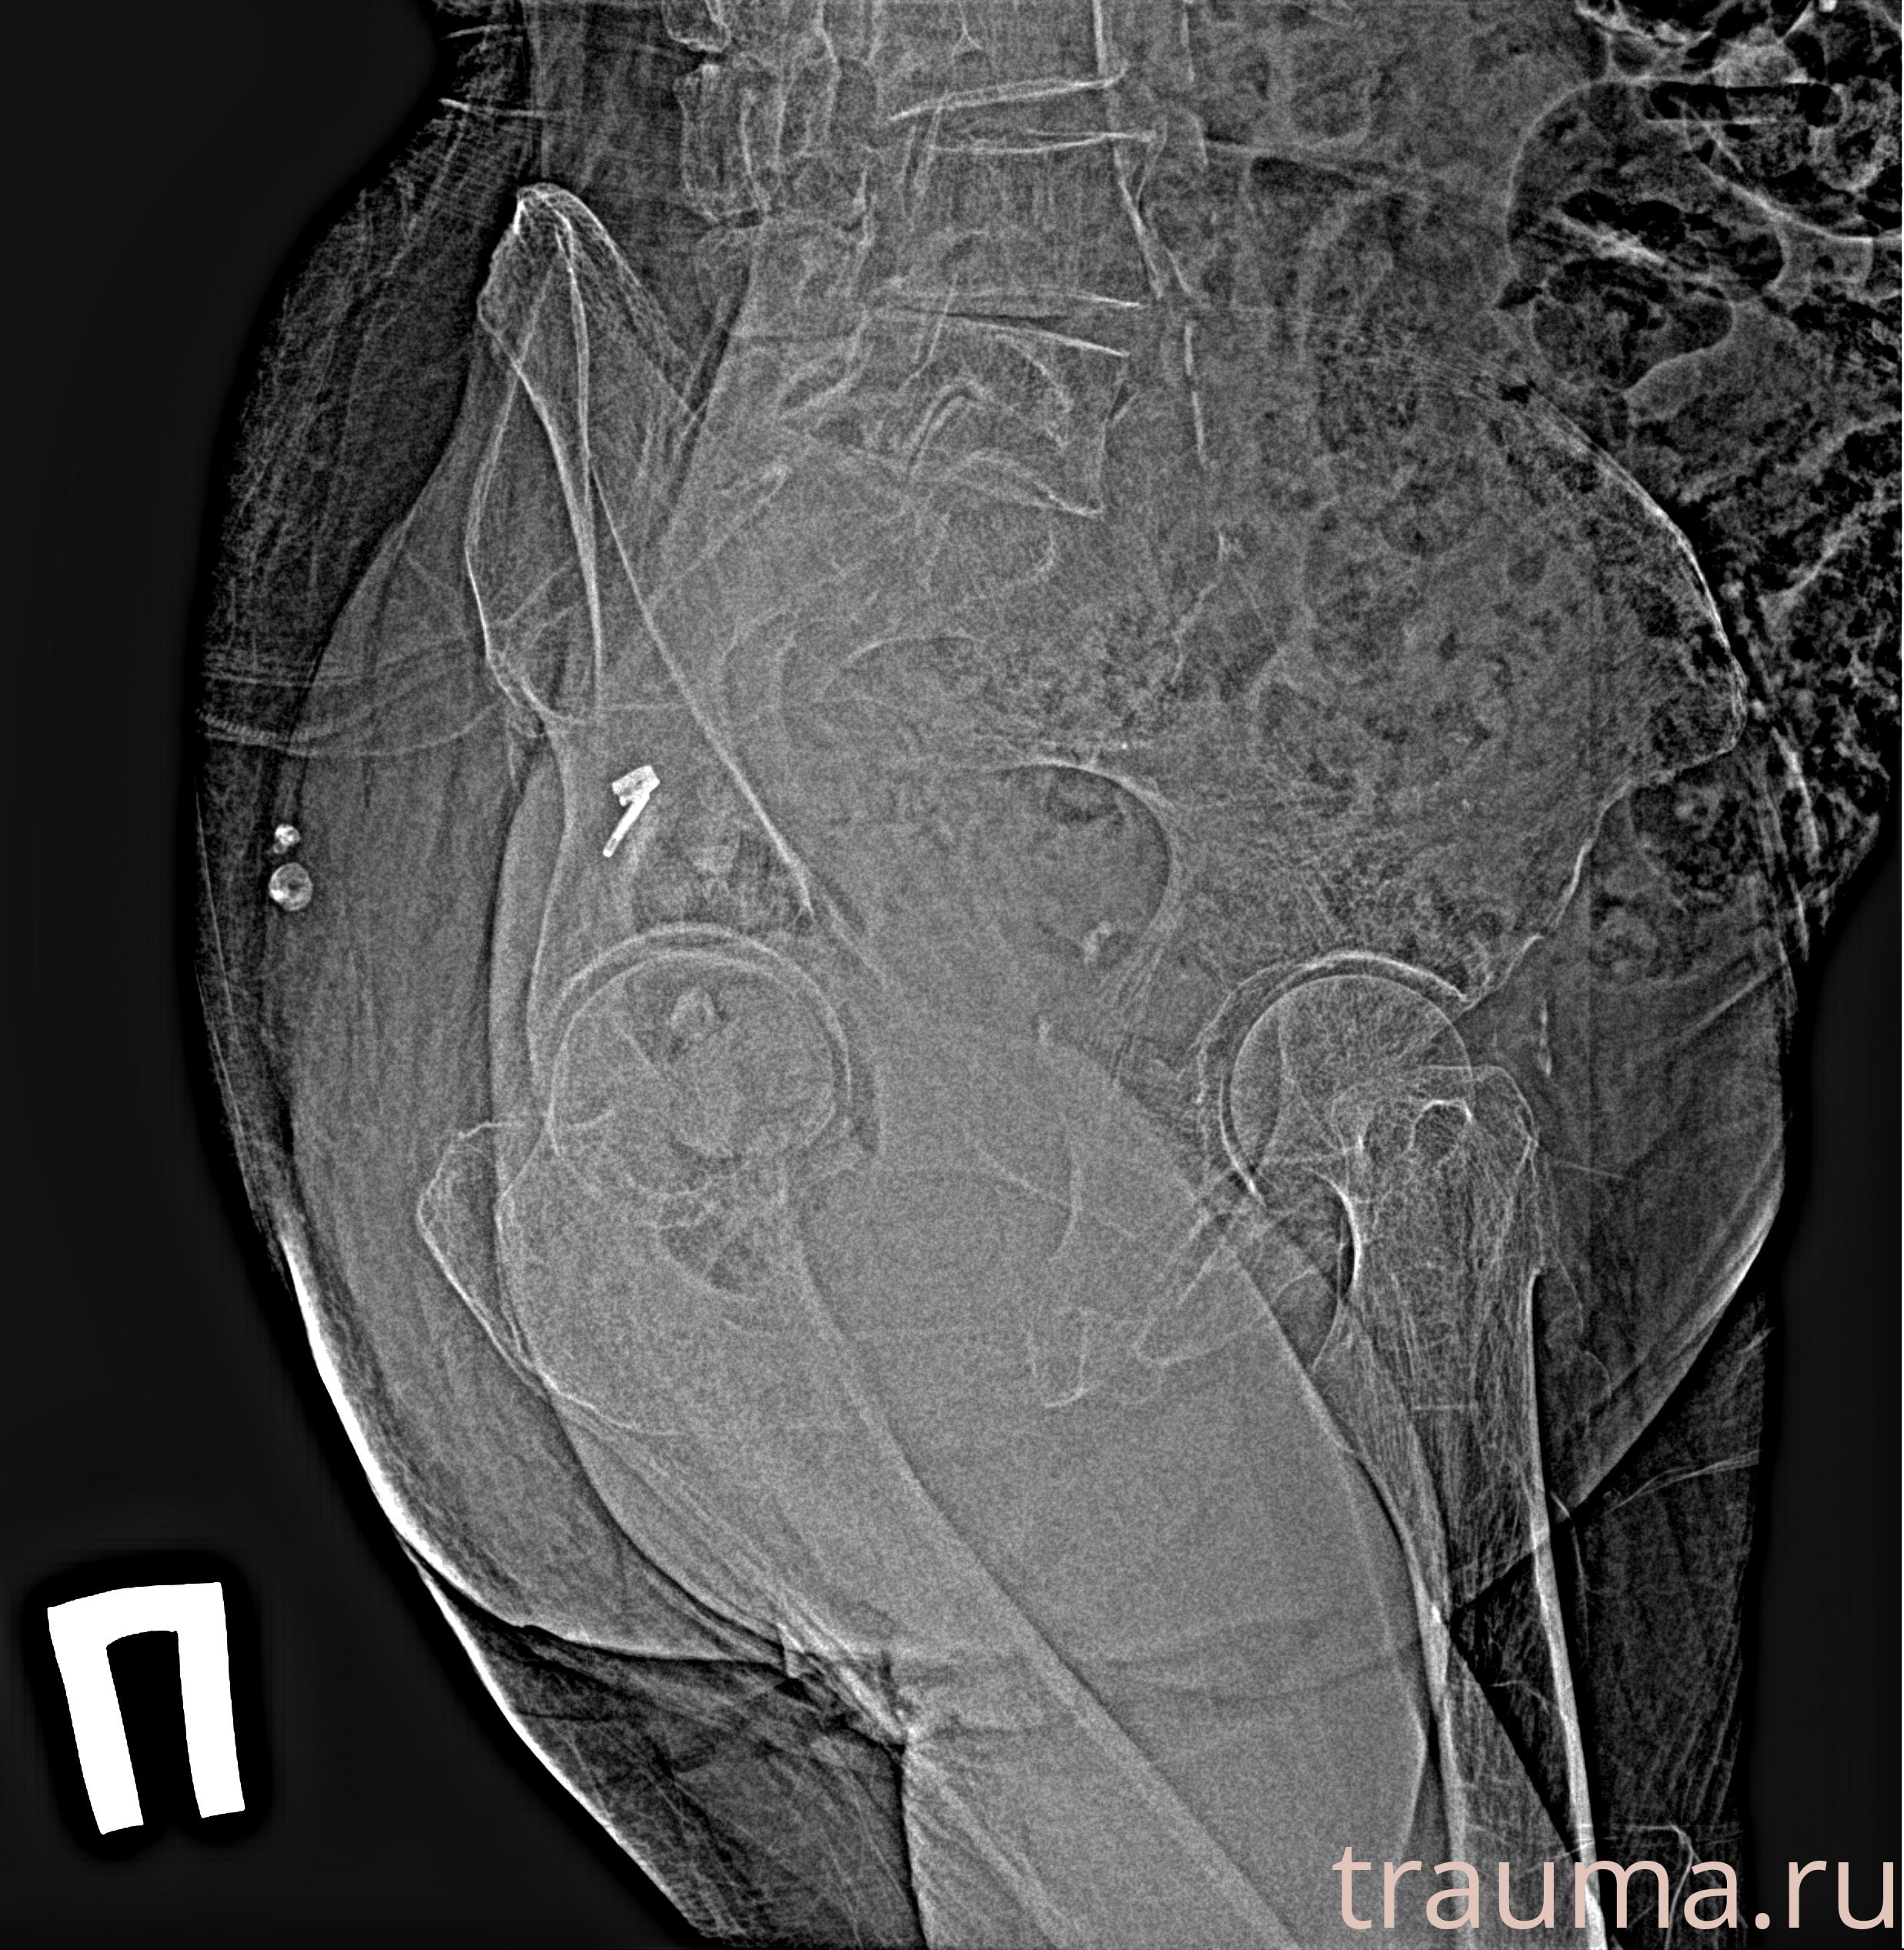

Рентген на дому: по вашему адресу приезжает врач-рентгенолог, травматолог-ортопед с мобильным рентгеновским аппаратом, проводит диагностику травмы или заболевания, делает необходимые рентгенограммы, дает рекомендации по дальнейшему лечению. Получить качественные снимки в домашних условиях возможно благодаря уникальной методике, разработанной МосРентген Центром для института  Склифосовского